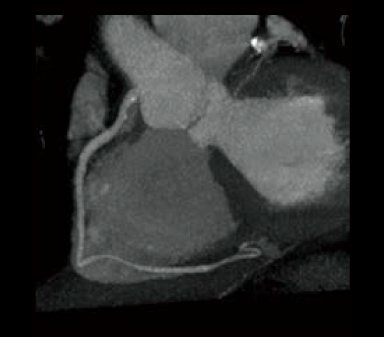

Dans les examens TDM cardiaques, les différents facteurs tels que la fréquence cardiaque et les mouvements du cœur affectent la qualité de l’image. Avec les méthodes conventionnelles de reconstruction d’image, des artères coronaires non focalisées et des artefacts causés par le mouvement peuvent apparaître, ce qui se traduit par des images ne répondant pas à la qualité attendue, ce qui peut affecter le diagnostic. Pour résoudre ces problèmes, Fujifilm a développé Cardio StillShot, qui calcule la direction et la quantité de mouvement du sujet en quatre dimensions à partir des données brutes collectées pendant les examens TDM cardiaques, et les corrige pendant la reconstruction de l’image pour obtenir une résolution temporelle effective de 28 msec.*1 La résolution temporelle effective contribue à améliorer la capacité de diagnostic en fournissant des images cliniques focalisées de haute définition avec moins d’artefacts de mouvement, même chez les patients ayant une fréquence cardiaque élevée.

Cardio StillShot : OFF

Cardio StillShot : ON